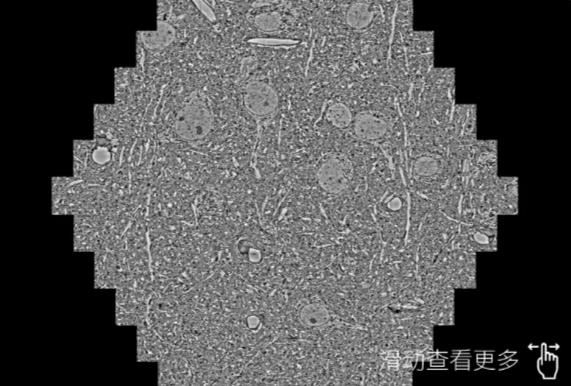

鼠脑切片。左图使用吕梁蔡司吕梁扫描电镜MultiSEM706对165μmx143pm面积区域成像,耗时仅需1.5秒。右图为鼠脑切片中30μm区域放大效果。样品由芝加哥大学B.Kasthuri提供。